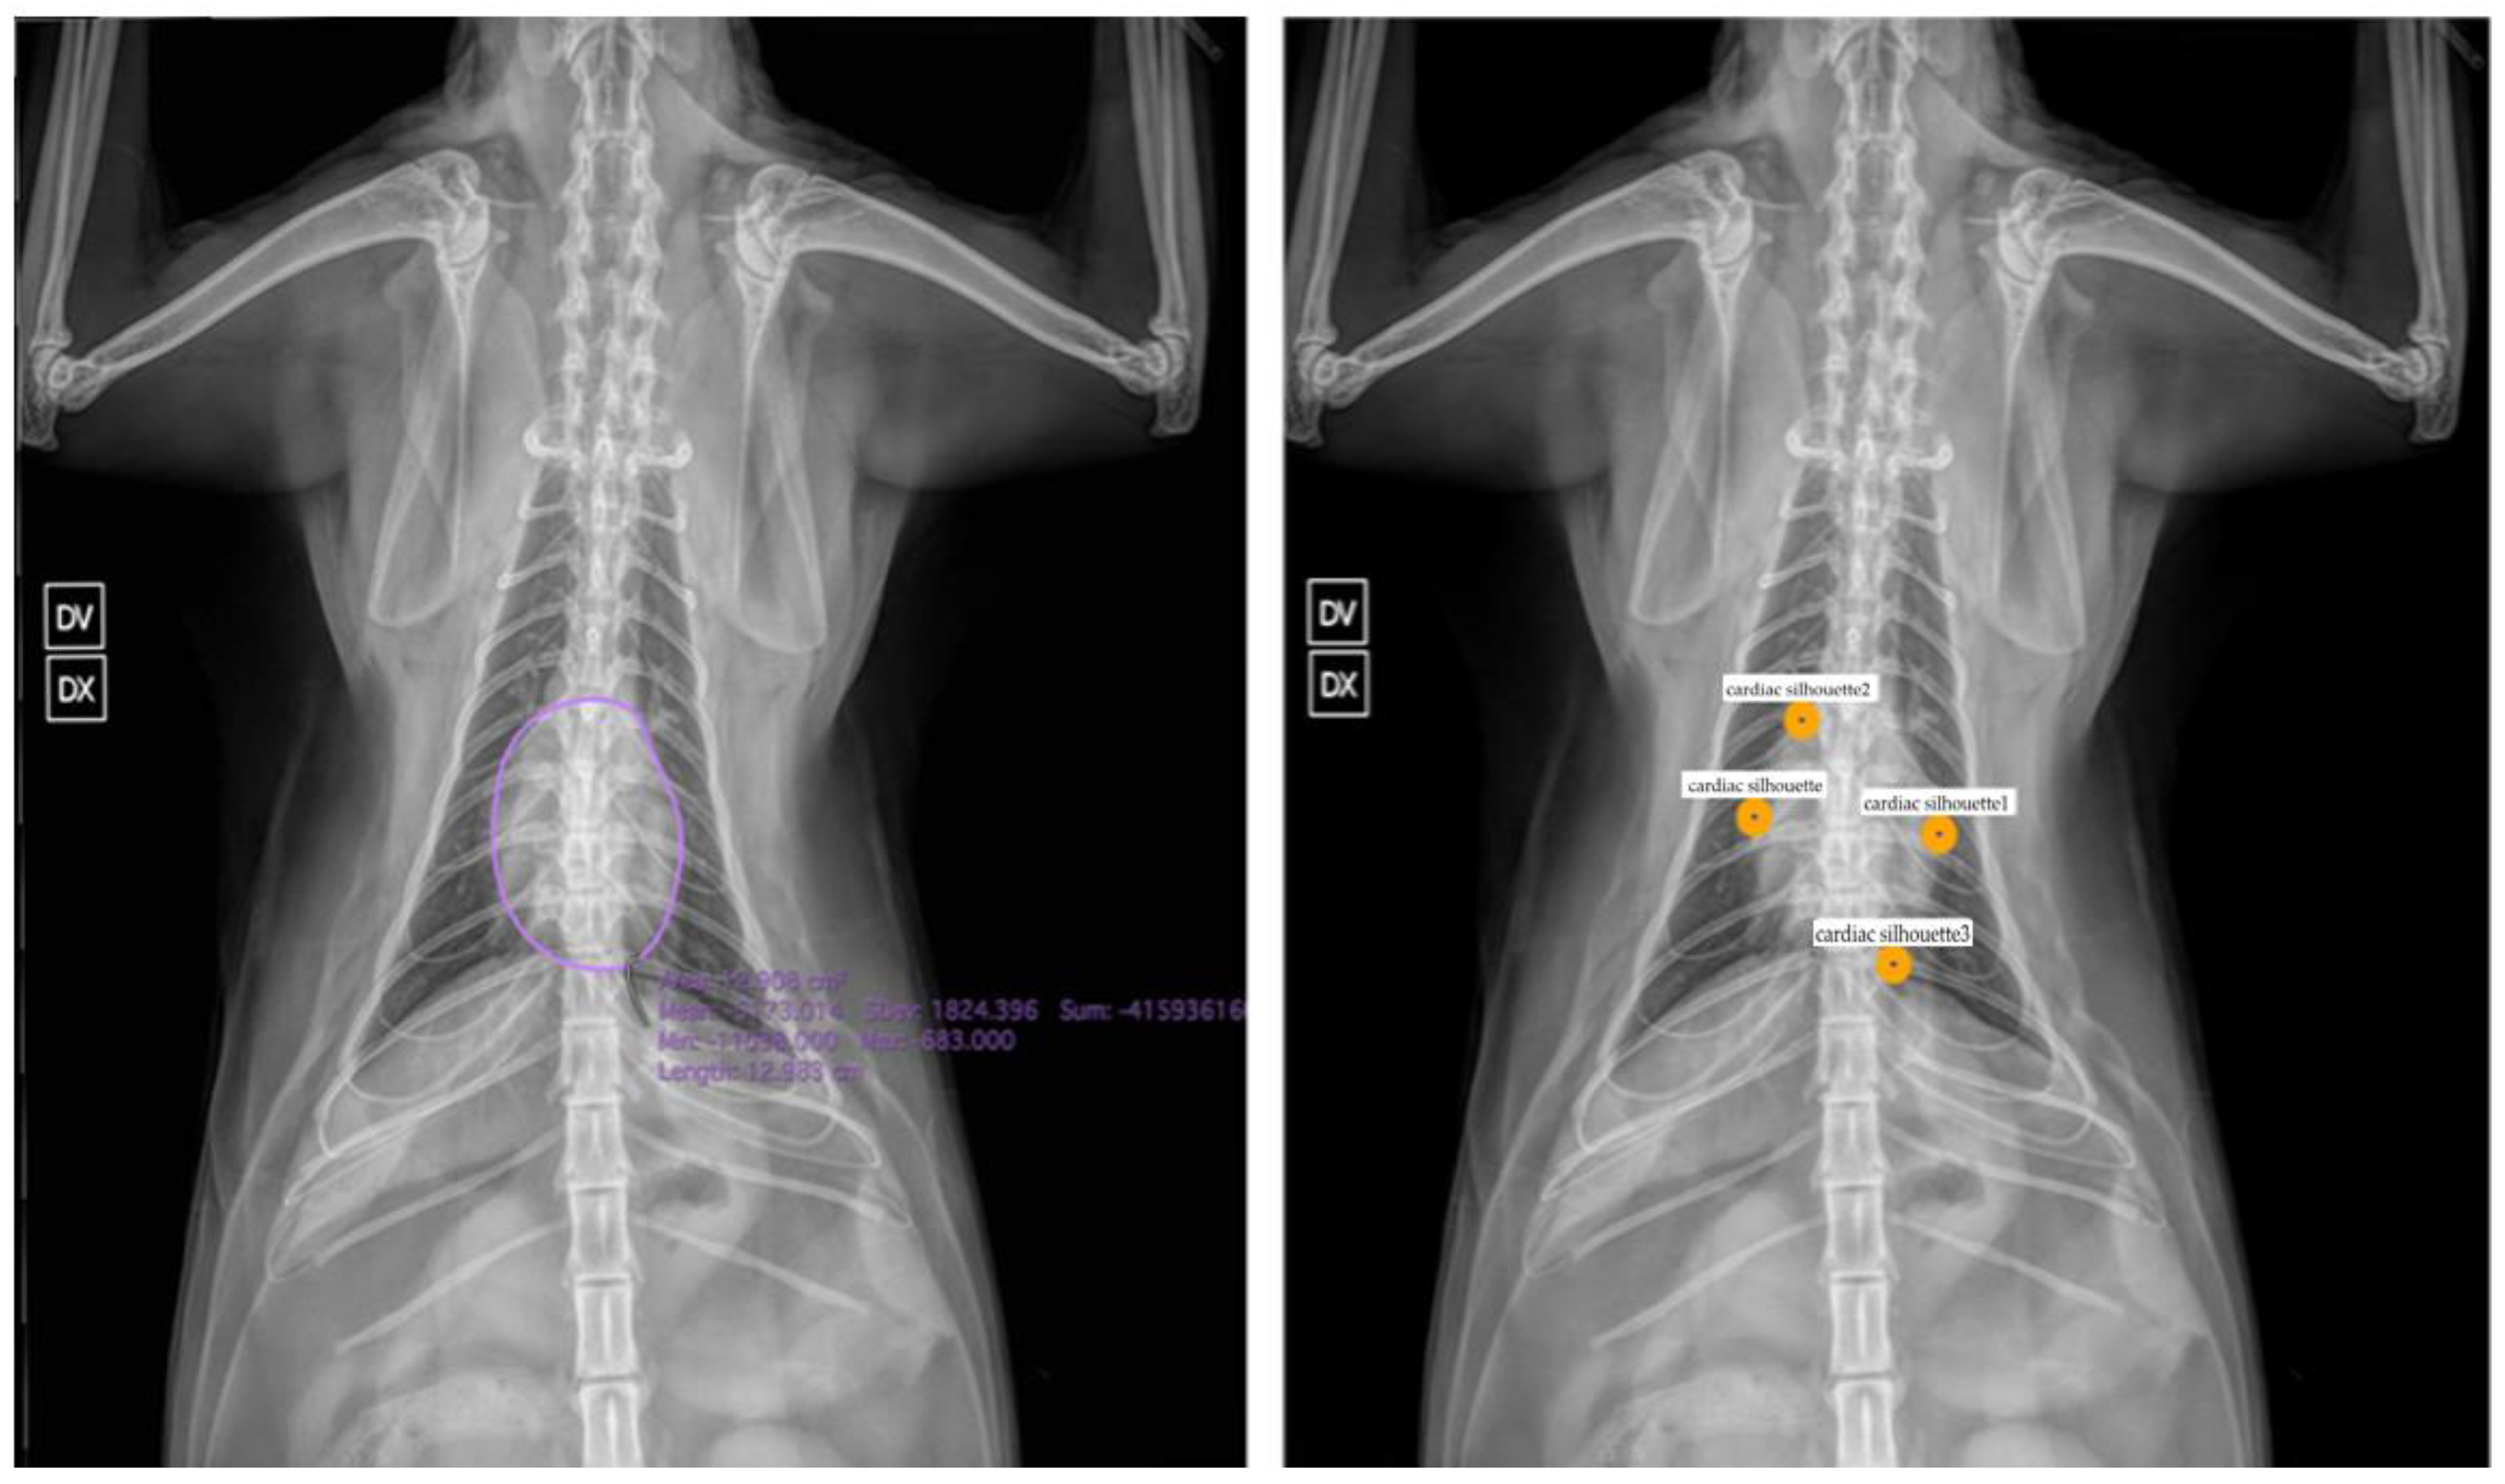

| Yoon et al., 2018 [40] | Normal vs. abnormal cardiac silhouette and thoracic portions | Dog |